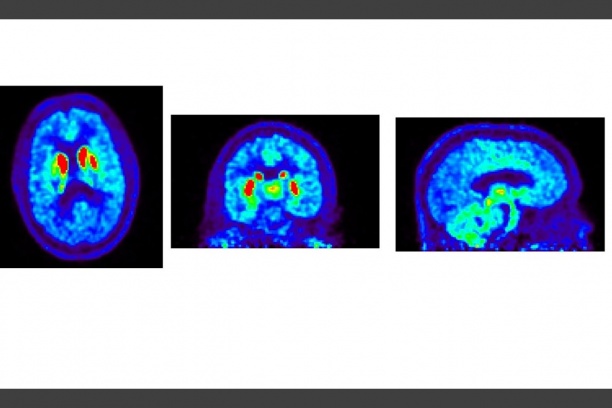

ADNI 4- The Alzheimer's Disease Neuroimaging Initiative study